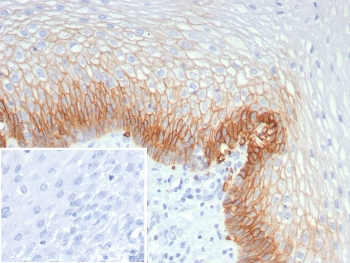

IHC staining of FFPE human esophagus tissue with SLC2A1 antibody (clone GLUT1/7308). Inset: PBS used in place of primary Ab (secondary Ab negative control). HIER: boil tissue sections in pH9 10 mM Tris with 1 mM EDTA for 20 min and allow to cool before testing.